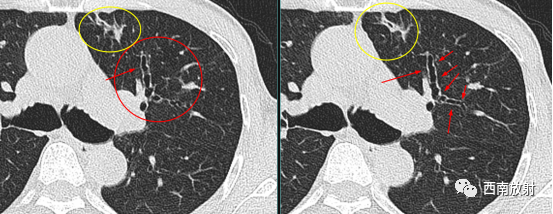

黏液嵌塞征是支气管扩张症比较少见的征象,是由于支气管分泌物贮留于扩张的支气管内所致。支气管扩张症也可伴有叶段的肺萎缩,表现为较大的肺动脉和主或叶支气管的移位,邻近肺段内的支气管和肺血管结构的重新排列,在萎缩肺中可见增粗的含气支气管征。

▲图:黄箭头及圆圈:静脉曲张样支气管扩张,双轨征;黄圈:支气管粘液栓塞。